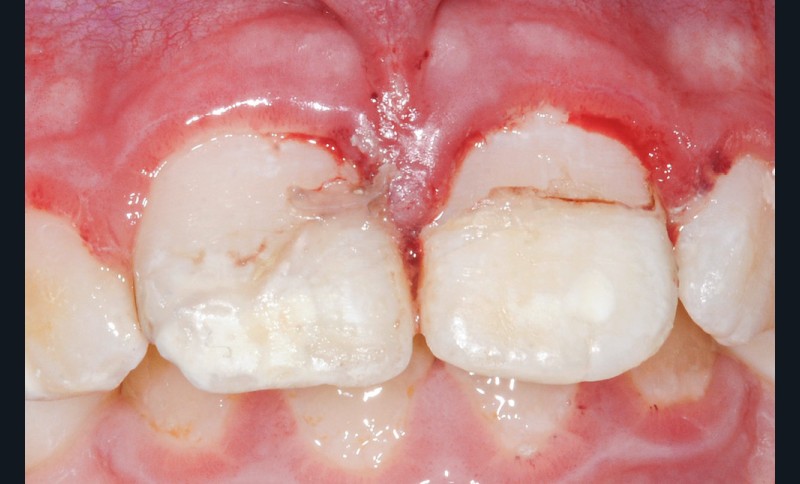

Les fragments sont placés dans du sérum physiologique afin de les réhydrater et d’augmenter leur potentiel d’adhésion. Dans un premier temps, des anesthésies locales en para-apicale de 11 et 21 sont réalisées. Des anesthésies de contact à l’aide d’un gel lidocaïné ou d’une cryoanesthésie peuvent être faites en amont pour diminuer les sensations désagréables de l’anesthésie locale. L’étape suivante consiste en la mise en place du champ opératoire. Au niveau du secteur antérieur, la mise en place d’une feuille de digue maintenue par des cordonnets élastiques de stabilisation (Wedjet™) est souvent réalisable. Sa mise en place est rapide et évite la pose d’un crampon sur des dents impliquées dans le traumatisme. Un crampon sur la 55 est également placé afin de maintenir la digue. L’étanchéité obtenue n’est pas toujours idéale et des spécificités liées à l’enfant compliquent sa mise en place, comme ici des dents malpositionnées ou en cours d’éruption (fig. 4). Après un nettoyage des dents fracturées et des fragments à replacer, une vérification du repositionnement correct de ces fragments est effectuée. Une pulpotomie partielle d’une profondeur d’un millimètre est réalisée sur la 11 à l’aide d’une fraise boule diamantée. Un biomatériau de type biocéramique (Biodentine™) vient coiffer la pulpe de 11 et 21 (fig. 5). Les bords amélaires sont ensuite soigneusement nettoyés à l’aide d’une microbrossette. En effet, l’adhésion se fera principalement entre l’émail de la dent fracturée et l’émail du fragment. L’épaisseur de biocérmique est réduite pour être la plus fine possible.